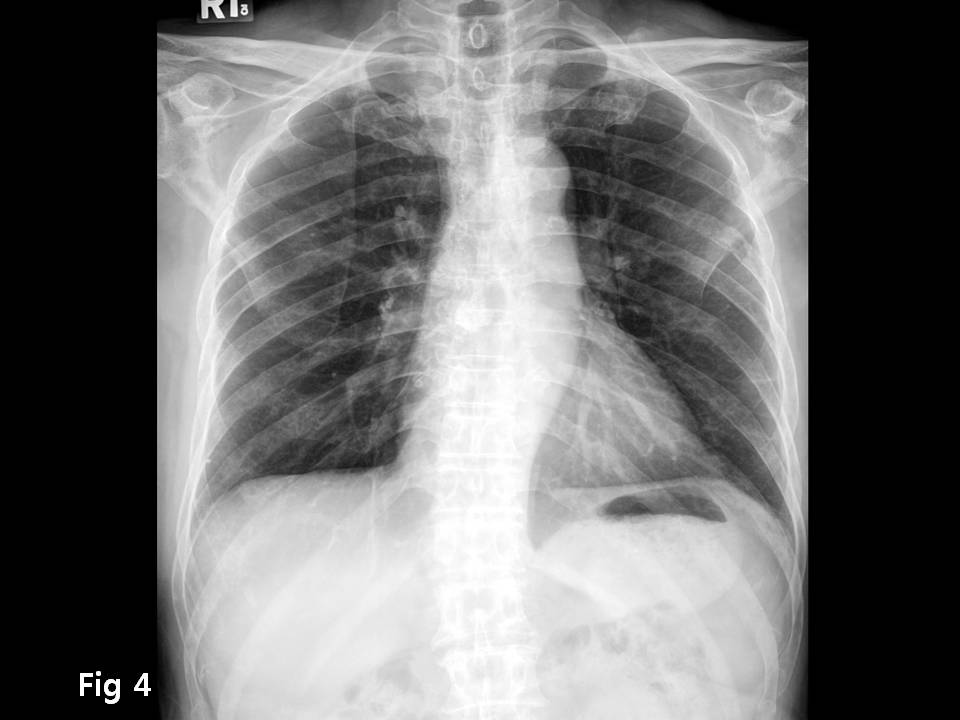

M/70

Chest pain  È£¼Ò

Chest CT ¿Ã·Á ÁÖ¼¼¿ä